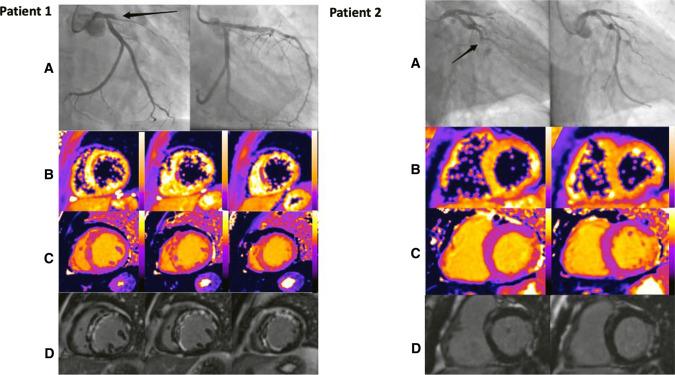

The effect of limb remote ischaemic conditioning (RIC) on myocardial infarct (MI) size and left ventricular ejection fraction (LVEF) was investigated in a pre-planned cardiovascular magnetic resonance (CMR) substudy of the CONDI-2/ERIC-PPCI trial. This single-blind multi-centre trial (7 sites in UK and Denmark) included 169 ST-segment elevation myocardial infarction (STEMI) patients who were already randomised to either control (n = 89) or limb RIC (n = 80) (4 × 5 min cycles of arm cuff inflations/deflations) prior to primary percutaneous coronary intervention. CMR was performed acutely and at 6 months. The primary endpoint was MI size on the 6 month CMR scan, expressed as median and interquartile range. In 110 patients with 6-month CMR data, limb RIC did not reduce MI size [RIC: 13.0 (5.1-17.1)% of LV mass; control: 11.1 (7.0-17.8)% of LV mass, P = 0.39], or LVEF, when compared to control. In 162 patients with acute CMR data, limb RIC had no effect on acute MI size, microvascular obstruction and LVEF when compared to control. In a subgroup of anterior STEMI patients, RIC was associated with lower incidence of microvascular obstruction and higher LVEF on the acute scan when compared with control, but this was not associated with an improvement in LVEF at 6 months. In summary, in this pre-planned CMR substudy of the CONDI-2/ERIC-PPCI trial, there was no evidence that limb RIC reduced MI size or improved LVEF at 6 months by CMR, findings which are consistent with the neutral effects of limb RIC on clinical outcomes reported in the main CONDI-2/ERIC-PPCI trial.